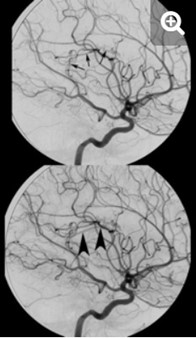

Los estudios de TC permiten evidenciar los accidentes cerebrovasculares (ACV) ocasionados por el abuso de la cocaína. Por caso, se localizó en la literatura imágenes que permiten ver el ACV isquémico agudo de la arteria cerebral media izquierda de un paciente. La TC sin contraste intravenoso visualiza la hipodensidad de la cabeza del caudado, del núcleo lenticular y de la ínsula izquierda. También se realizaron estudios de RM, que permiten observar la restricción del área isquémica en el territorio silviano(18) (ver Imagen 5).

Los consumidores habituales de cocaína suelen tener un pico de presión arterial sistólica elevada y un aumento de la frecuencia cardíaca tras el consumo, que los hace propensos a sufrir malformaciones arterovenosas. Al mismo tiempo, si esta sustancia se combina con etanol, las probabilidad de padecer una hemorragia subaracnoidea se incrementan. A propósito, se puede mencionar el caso de una paciente de 33 años de edad con síntomas de cefalea intensa y hemiparesia izquierda, en cuyo análisis de tóxicos de orina se detectó cocaína.(18)

En el caso que se viene reseñando, se realizó TC sin contraste para evidenciar eventuales daños isquémicos. En este estudio se localizó un hematoma intraparenquimatoso (ver Imagen 6). Este tipo de hematomas tiene un significativo riesgo para la persona, dado que puede avanzar hacia hemorragias con daño en la barrera hematoencefálica e incremento de la presión intracraneal, que puede ocasionar déficit neurológico e incluso la muerte.(17, 18)

En los casos de personas sin patología vascular subyacente, las hemorragias intraparenquimatosas se localizan con mayor frecuencia en los ganglios basales y el tálamo. Un caso como este se obtuvo en la literatura, correspondiente a una mujer de 23 años que sufrió una hemiplejía completa. Se le localizaron cantidades considerables de cocaína en el análisis de orina. La RM evidenció una isquemia en la rama MCA derecha con afectación de los ganglios basales(17) (ver Imagen 7).

Otro caso que conviene referir es el de una mujer de 19 años, quien acudió al servicio de guardia por dolor de cabeza agudo. Se le realizó una TC que mostró una hemorragia intraventricular con un posible componente parenquimatoso cerca de la pared del ventrículo derecho, a partir del abuso de cocaína en combinación con alcohol (ver Imagen 8). De igual modo, la angiografía evidenció una malformación arteriovenosa coroidea alimentada por la arteria coroidea lateral posterior(17) (ver Imagen 9).